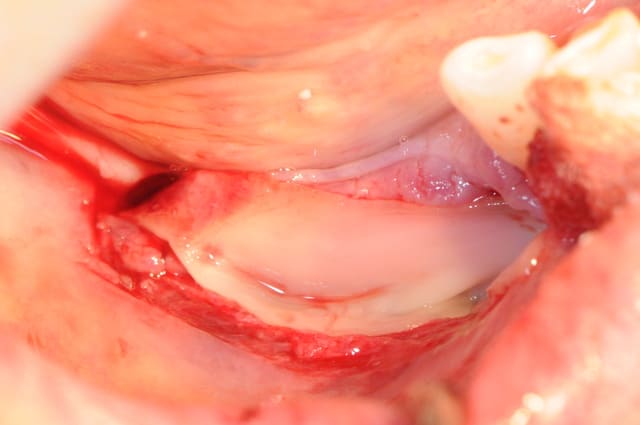

seulement aujourd'hui, la tréphine apès avoir traversé la corticale est rentrée comme dans du beurre. j'ai été surpris car je faisait très attention. la patiente n'a absolument pas bronché d'un cil. quand j'ai retiré la carotte il y avait un truc mou accroché dessous; le V3 !

on voit même sur la carotte la trace du nerf (photo)